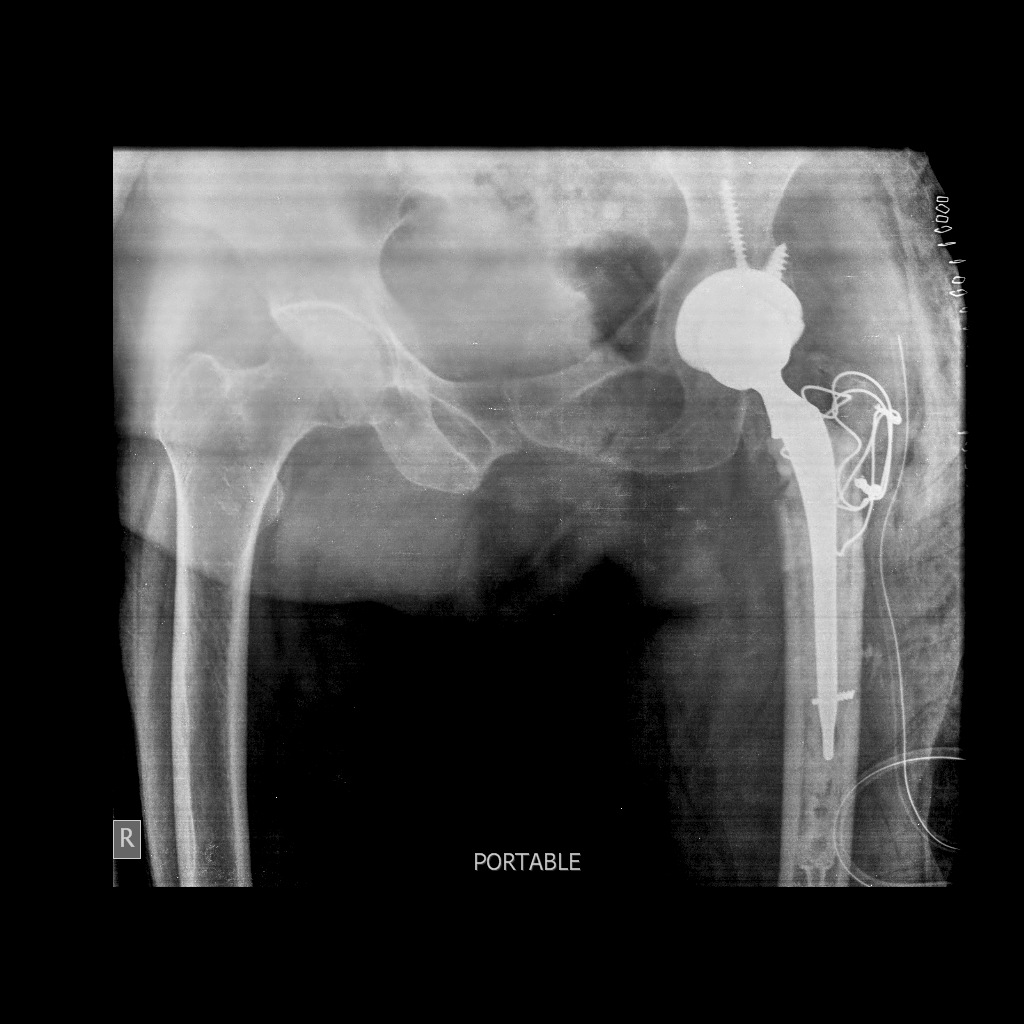

Protocol of managing patients undergoing uncemented total hip

Uncemented Total Hip Replacement DHS to THR ( Conversion THR) Dr Hip Replacement Post Op Care if you have just undergone hip surgery, this article is designed to provide you with general advice on how to manage. measures to prevent clots in the leg need to be taken following hip replacement, normally continuing for about six weeks. “when can i…?” answers for hip replacement patients. what to expect after hip replacement surgery. The. Hip Replacement Post Op Care.

From www.researchgate.net

Clinical images Total Hip Replacement Hip Replacement Post Op Care what to expect after hip replacement surgery. Complete recovery from a hip replacement surgery is a long process,. “when can i…?” answers for hip replacement patients. also called total hip arthroplasty, hip replacement surgery might be an option if hip pain interferes with. postoperative care for hip replacement. measures to prevent clots in the leg need. Hip Replacement Post Op Care.